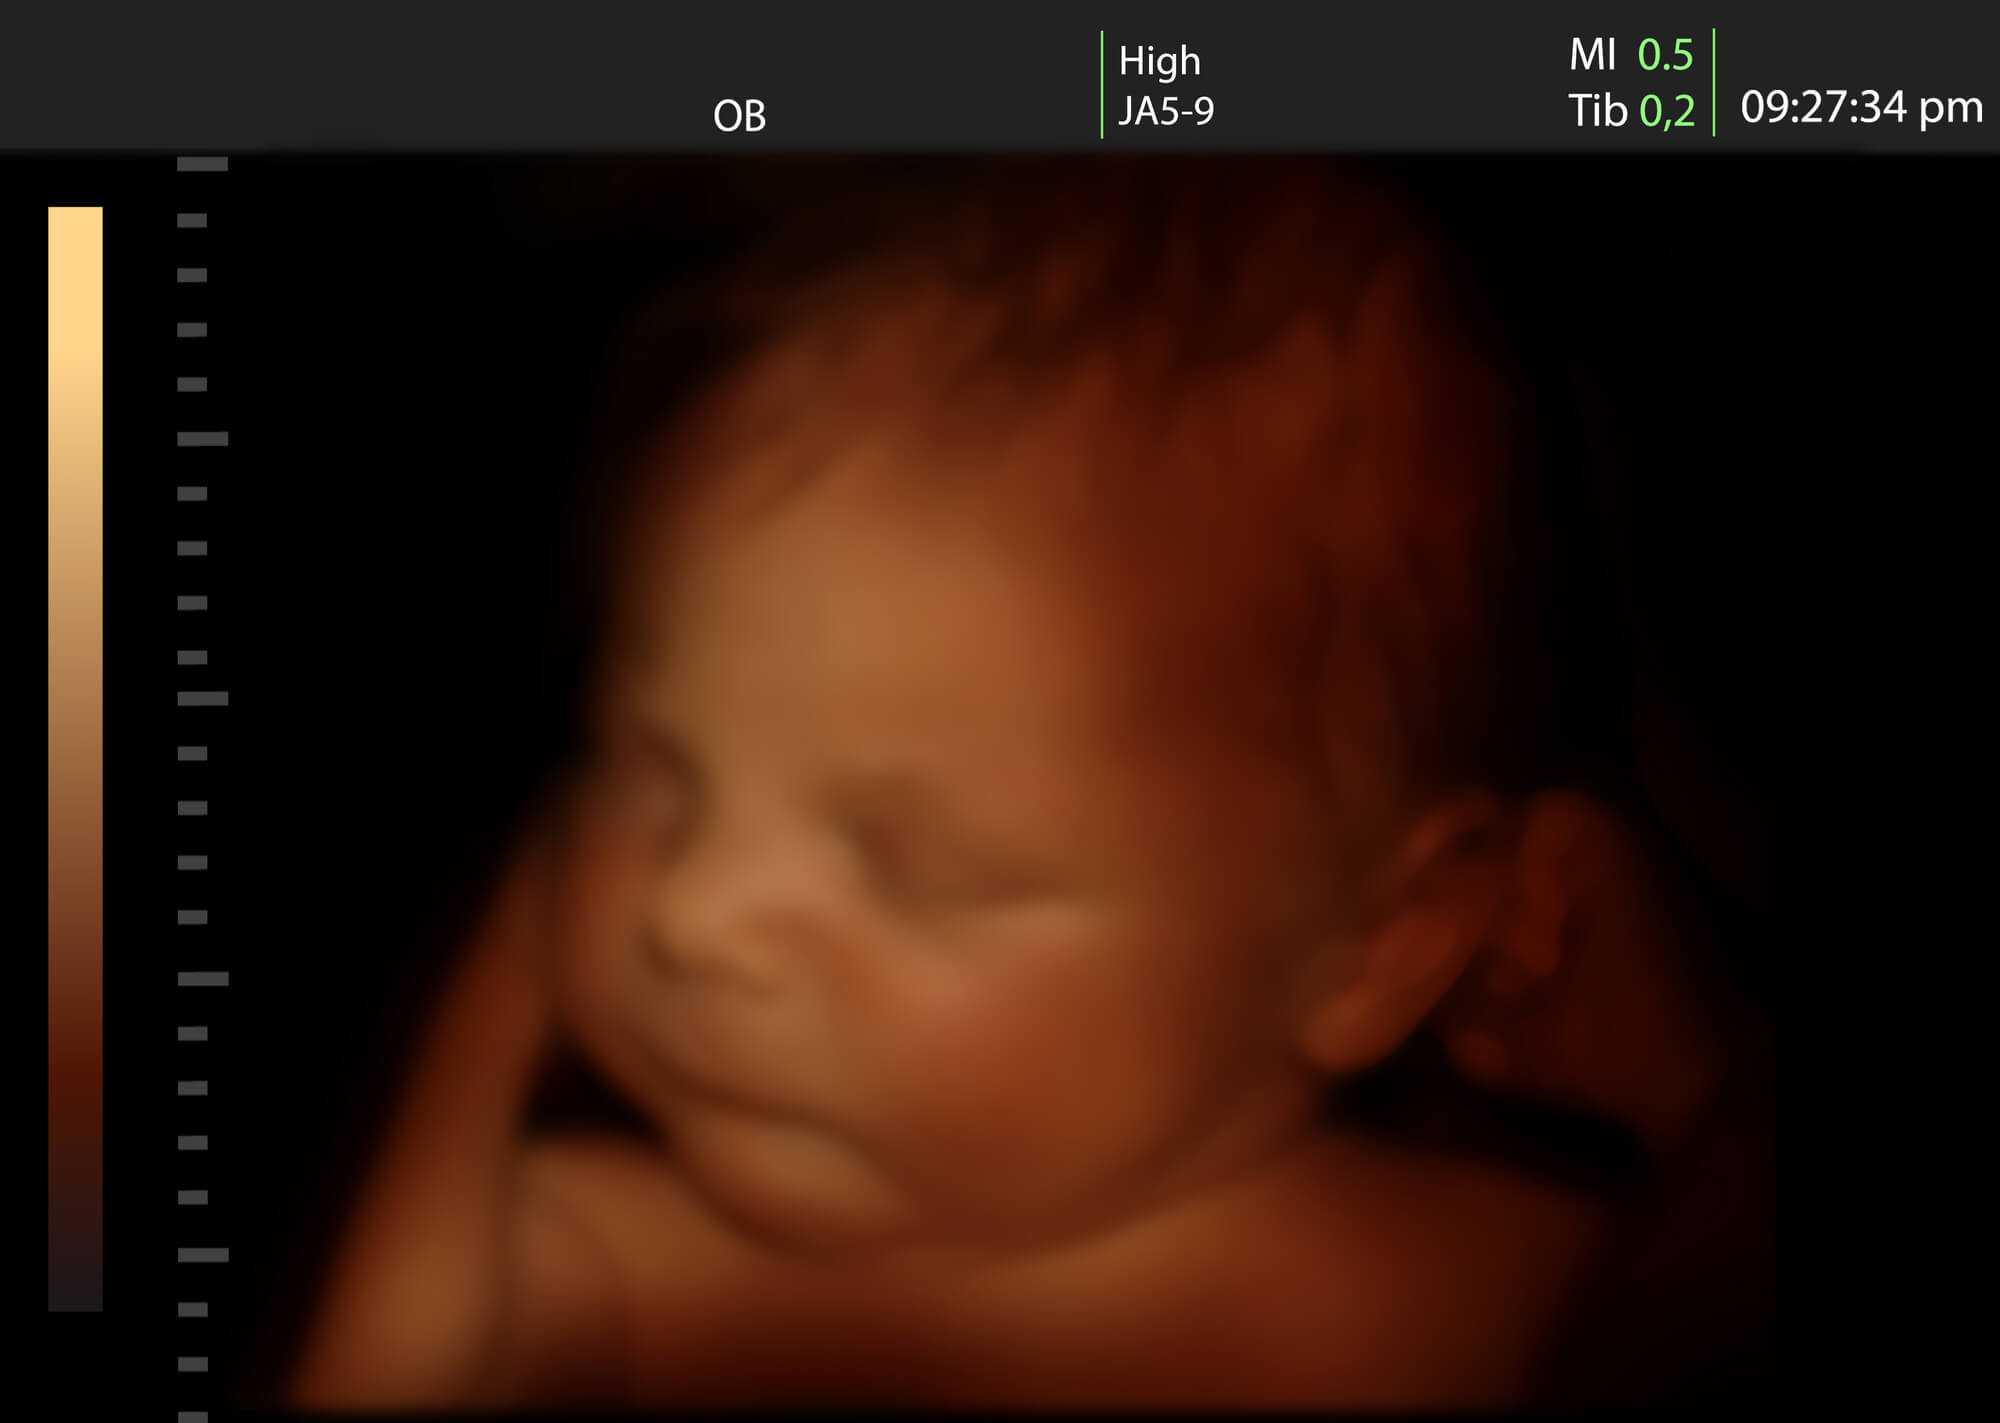

USG ciąży 3D to badanie diagnostyczne przeprowadzane z wykorzystaniem aparatury ultrasonograficznej. Pozwala na uzyskanie trójwymiarowego obrazu płodu oraz wnętrza macicy. Takie badanie zaleca się wykonać ok. 28 tygodnia ciąży.

Jedną z największych korzyści wykonania badania USG ciąży 3D jest możliwość przestrzennej wizualizacji ciała dziecka (w tym jego płci), co niezaprzeczalnie jest bardzo korzystnego dla przyszłych rodziców. Dzięki badaniu można zaobserwować takie szczegóły jak mimika płodu, ułożenie kończyn czy paluszków. Dla przyszłych rodziców dziecka obraz uzyskany w obrazowaniu 3D może być dla nich bardzo wzruszający, ponieważ można wówczas zaobserwować jak dziecko ziewa, się uśmiecha czy macha rączkami. Jest to ważne z psychologicznego punktu widzenia, ponieważ ma to bardzo duże znaczenie w tworzeniu więzi emocjonalnej między dzieckiem a rodzicami.

Z medycznego punktu widzenia USG ciąży 3D ma istotną przewagę nad USG ciąży 2D w dokładnym obrazowaniu i określeniu typu rozszczepów podniebienia. Ponadto USG ciąży 3D jest doskonałym narzędziem diagnostycznym, które pozwala lekarzowi na ocenę kształtu głowy, twarzy, umiejscowienia uszu i rozpoznania płci. Dokładny obraz badania jest bardzo ważny w przypadku oceny rozwoju kończyn, kręgosłupa i powłok brzucha. Lekarz może także podejrzeć serce płody w kliku płaszczyznach i dokonać oceny rozwoju układu nerwowego. USG ciąży 3D jest bardzo dobrą metodą do diagnozowania wad genetycznych i wrodzonych płodu, tj. rozszczep kręgosłupa, wady serca i wyżej wspominany rozszczep podniebienia. Warto dodać, że badanie USG 3D jest pomocne w rozpoznawaniu zespołu Downa, dzięki możliwości pomiaru długości kości nosowej.